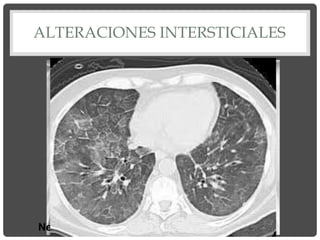

ALTERACIONES INTERSTICIALES

Neumopatía atípica: Mycoplasma pneumoniae

Patrón agudo de afectación intersticial

“en vidrio esmerilado”

Patrón Micronodulillar

TBC miliar

Patrón reticular

Fibrosis pulmonar

Panalización.

Patrón en “panal de abejas”.

Fibrosis pulmonar. Estadio final.